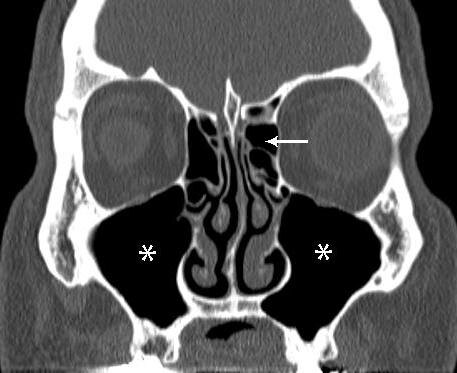

Корональная проекция. Срез через середину лица.

Первое, что бросается в глаза — полное затемнение. В норме воздушные, черные как ночное небо, верхнечелюстные пазухи по обеим сторонам от носовой перегородки теперь залиты густым молочным туманом. Это белое содежимое— признак не просто отека слизистой оболочки, а скопления густого, вязкого секрета, скорее всего гной, подумала Ксения Аркадьевна из собственного опыта

«Пансинусит», — мысленно констатирует Ксения, и ее взгляд становится жестче. Поражены не только верхнечелюстные, но и решетчатые ячейки — маленькие воздушные пещерки в глубине носа. На снимке они похожи на испещренную сотнями ячеек кость, но сейчас эти ячейки не черные, а серые, «запыленные». Это отек.

Здесь — ключ к пониманию катастрофы. В норме в нижней части каждой верхнечелюстной пазухи должно быть видно маленькое отверстие — естественное соустье, соединяющее пазуху с полостью носа. Оно — дверь для вентиляции и дренажа пазух носа. Сейчас эти двери забиты наглухо. На снимке вместо черного кружка — плотная белая «пробка» из отечной слизистой оболочки и густого секрета. Это обструкция остиомеатального комплекса — главная причина порочного круга: нет оттока -> скопление секрета -> рост давления -> усиление отека -> полная блокада.

Теперь отчетливо видна горизонтальный уровень жидкости. В правой пазухе — классическая картина: внизу, у «дна», плотное белое содержимое (гной), а над ним — узкая черная полоска воздуха. Левая пазуха заполнена полностью, без уровня — там процесс, возможно, начался раньше, и воздуха не осталось вовсе. «Двухсторонний гайморит», как говорят в простонародии.